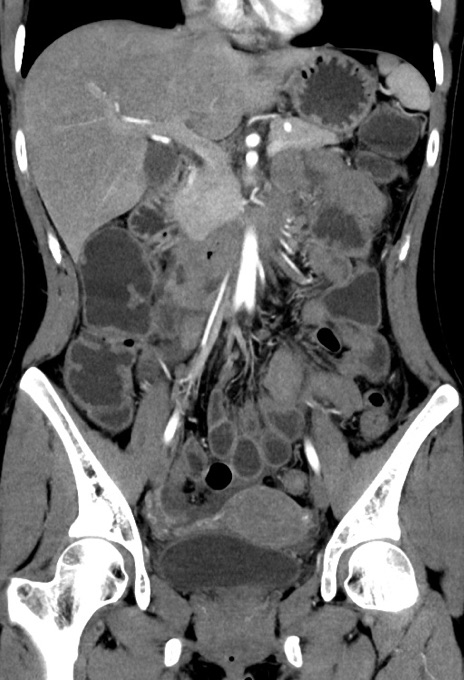

症例17(冠状断像)

【症例】20歳代女性

【主訴】嘔吐、下腹部痛

【現病歴】昨日夕食後に嘔吐し下腹部痛が出現。本日になっても嘔吐持続し改善しないため来院。

【身体所見】意識清明、BT 37.2℃、BP 108/67mmHg、腹部:平坦、やや硬、下腹部正中から右にかけて圧痛あり、反跳痛軽度あり、tapping pain(+)。

【データ】WBC 13600、CRP 14.94